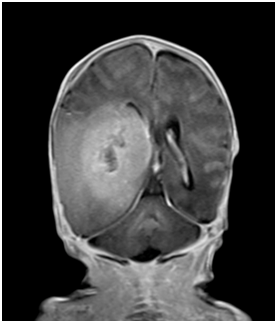

Ultrasound of the brain on day 1 of life showed a right parieto-occipital hypoechoic mass of 4.8 cm with 2.1 cm hyperechoic density (Figure 2). Magnetic Resonance Imaging (MRI) of the brain showed a large haemorrhagic right temporo-occipital mass measuring 5.6 cm, with early hydrocephalus, suspicious of a supratentorial primitive neuroectodermal tumour (PNET) (Figure 3).

Figure 3 MRI of baby brain showing heterogeneously enhancing large right hemispheric mass involving the ipsilateral temporal and occipital lobes. It measures 5.6 x 3.4 x 4.5 cm. The solid enhancing component shows restricted diffusion, indicative of cellularity. It causes significant mass effect on the adjacent cortical sulci, basal cisterns, body and occipital horn of the right lateral ventricle, resulting abnormal dilatation of both the temporal horns and occipital horn of the left lateral ventricle, indicative of early hydrocephalus. Midline shift was noted to the left side (2 mm). There was an intratumoural haemorrhagic component measures 2.0 x 4.0 cm. No significant surrounding edema was seen.

Other differential diagnosis of congenital solid tumour includes rare cases of primitive neuroectodermal tumour (PNET), choroid plexus papilloma, neuroblastoma, and gangliocytoma. PNETs are high grade malignant small-cell tumour and are thought to derive from the neural crest. It is characterized by early recurrence, metastasis, and high mortality.3 These tumours are frequently supratentorial, involving the cerebral hemispheres and pineal regions. On MRI scan, they are usually large heterogeneous masses that are hypointense on T2 and give restricted diffusion consistent with high cellularity. Perifocal edema may be scanty in spite of the huge size. In our case, MRI of the baby brain showed heterogeneous large right hemispheric mass with solid enhancing component showing restricted diffusion, indicative of cellularity. It causes significant mass effect, resulting in early hydrocephalus and midline shift. No significant surrounding edema was seen. Diagnosis is challenging with imaging alone and histology is usually needed for definite diagnosis. Because it is often deep-seated, PNET often poses significant challenges to safe resection. It is highly aggressive and very often therapy resistant in young children.6 Histology diagnosis was not possible in our patient as parents declined surgery or biopsy, and no post-mortem was performed. Molecular genetic studies of PNET are limited by the rare incidences and recurrence in subsequent pregnancies is unknown.